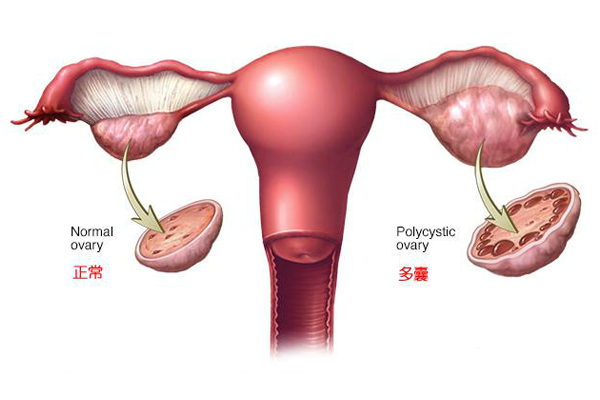

多囊卵巢综合征是一种常见的妇科疾病,也是试管婴儿常见的适应症,影响5-20%育龄女性,最常见的特征包括月经周期紊乱或延长、雄激素水平升高、卵巢出现大量囊肿,并最终...

多囊卵巢综合征(多囊卵巢综合症)是一种复杂的疾病,影响约10%的育龄妇女。患有多囊卵巢综合症的女性可能会出现各种症状,包括情绪变化和皮肤状况(痤疮,面部毛发过多)...

多囊卵巢综合症(PCOS)的特征表现为卵巢功能紊乱和高雄激素表现,是不孕症女性最常见的病因。PCOS女性常因月经紊乱而就诊于妇科医生,主诉多为高雄激素而产生的症状...

多囊卵巢综合征(PCOS)是以月经不规则(常见月经稀发、月经间期不规则阴道流血)、超声影像卵巢多囊改变和高雄激素血症为特征的综合征,是生育年龄妇女常见的代谢和内分...

多囊卵巢综合征(PCOS)是育龄期妇女最常见的内分泌和代谢紊乱性疾病,是引起无排卵性不孕的主要原因,一般认为它与遗传、胰岛素抵抗、下丘脑—垂体—卵巢轴功能异常、肾...

多囊卵巢综合征(PCOS)是一个女性常见的健康问题,影响约10%的育龄妇女。患有PCOS的女性有激素不平衡和新陈代谢问题,可能影响女性的整体健康和外貌。PCOS也...

多囊卵巢综合征(polycystic ovary syndrome,PCOS)是一种常见的青春期和育龄期妇女内分泌紊乱性疾病, 4%~18% 的育龄期妇女受其影响...